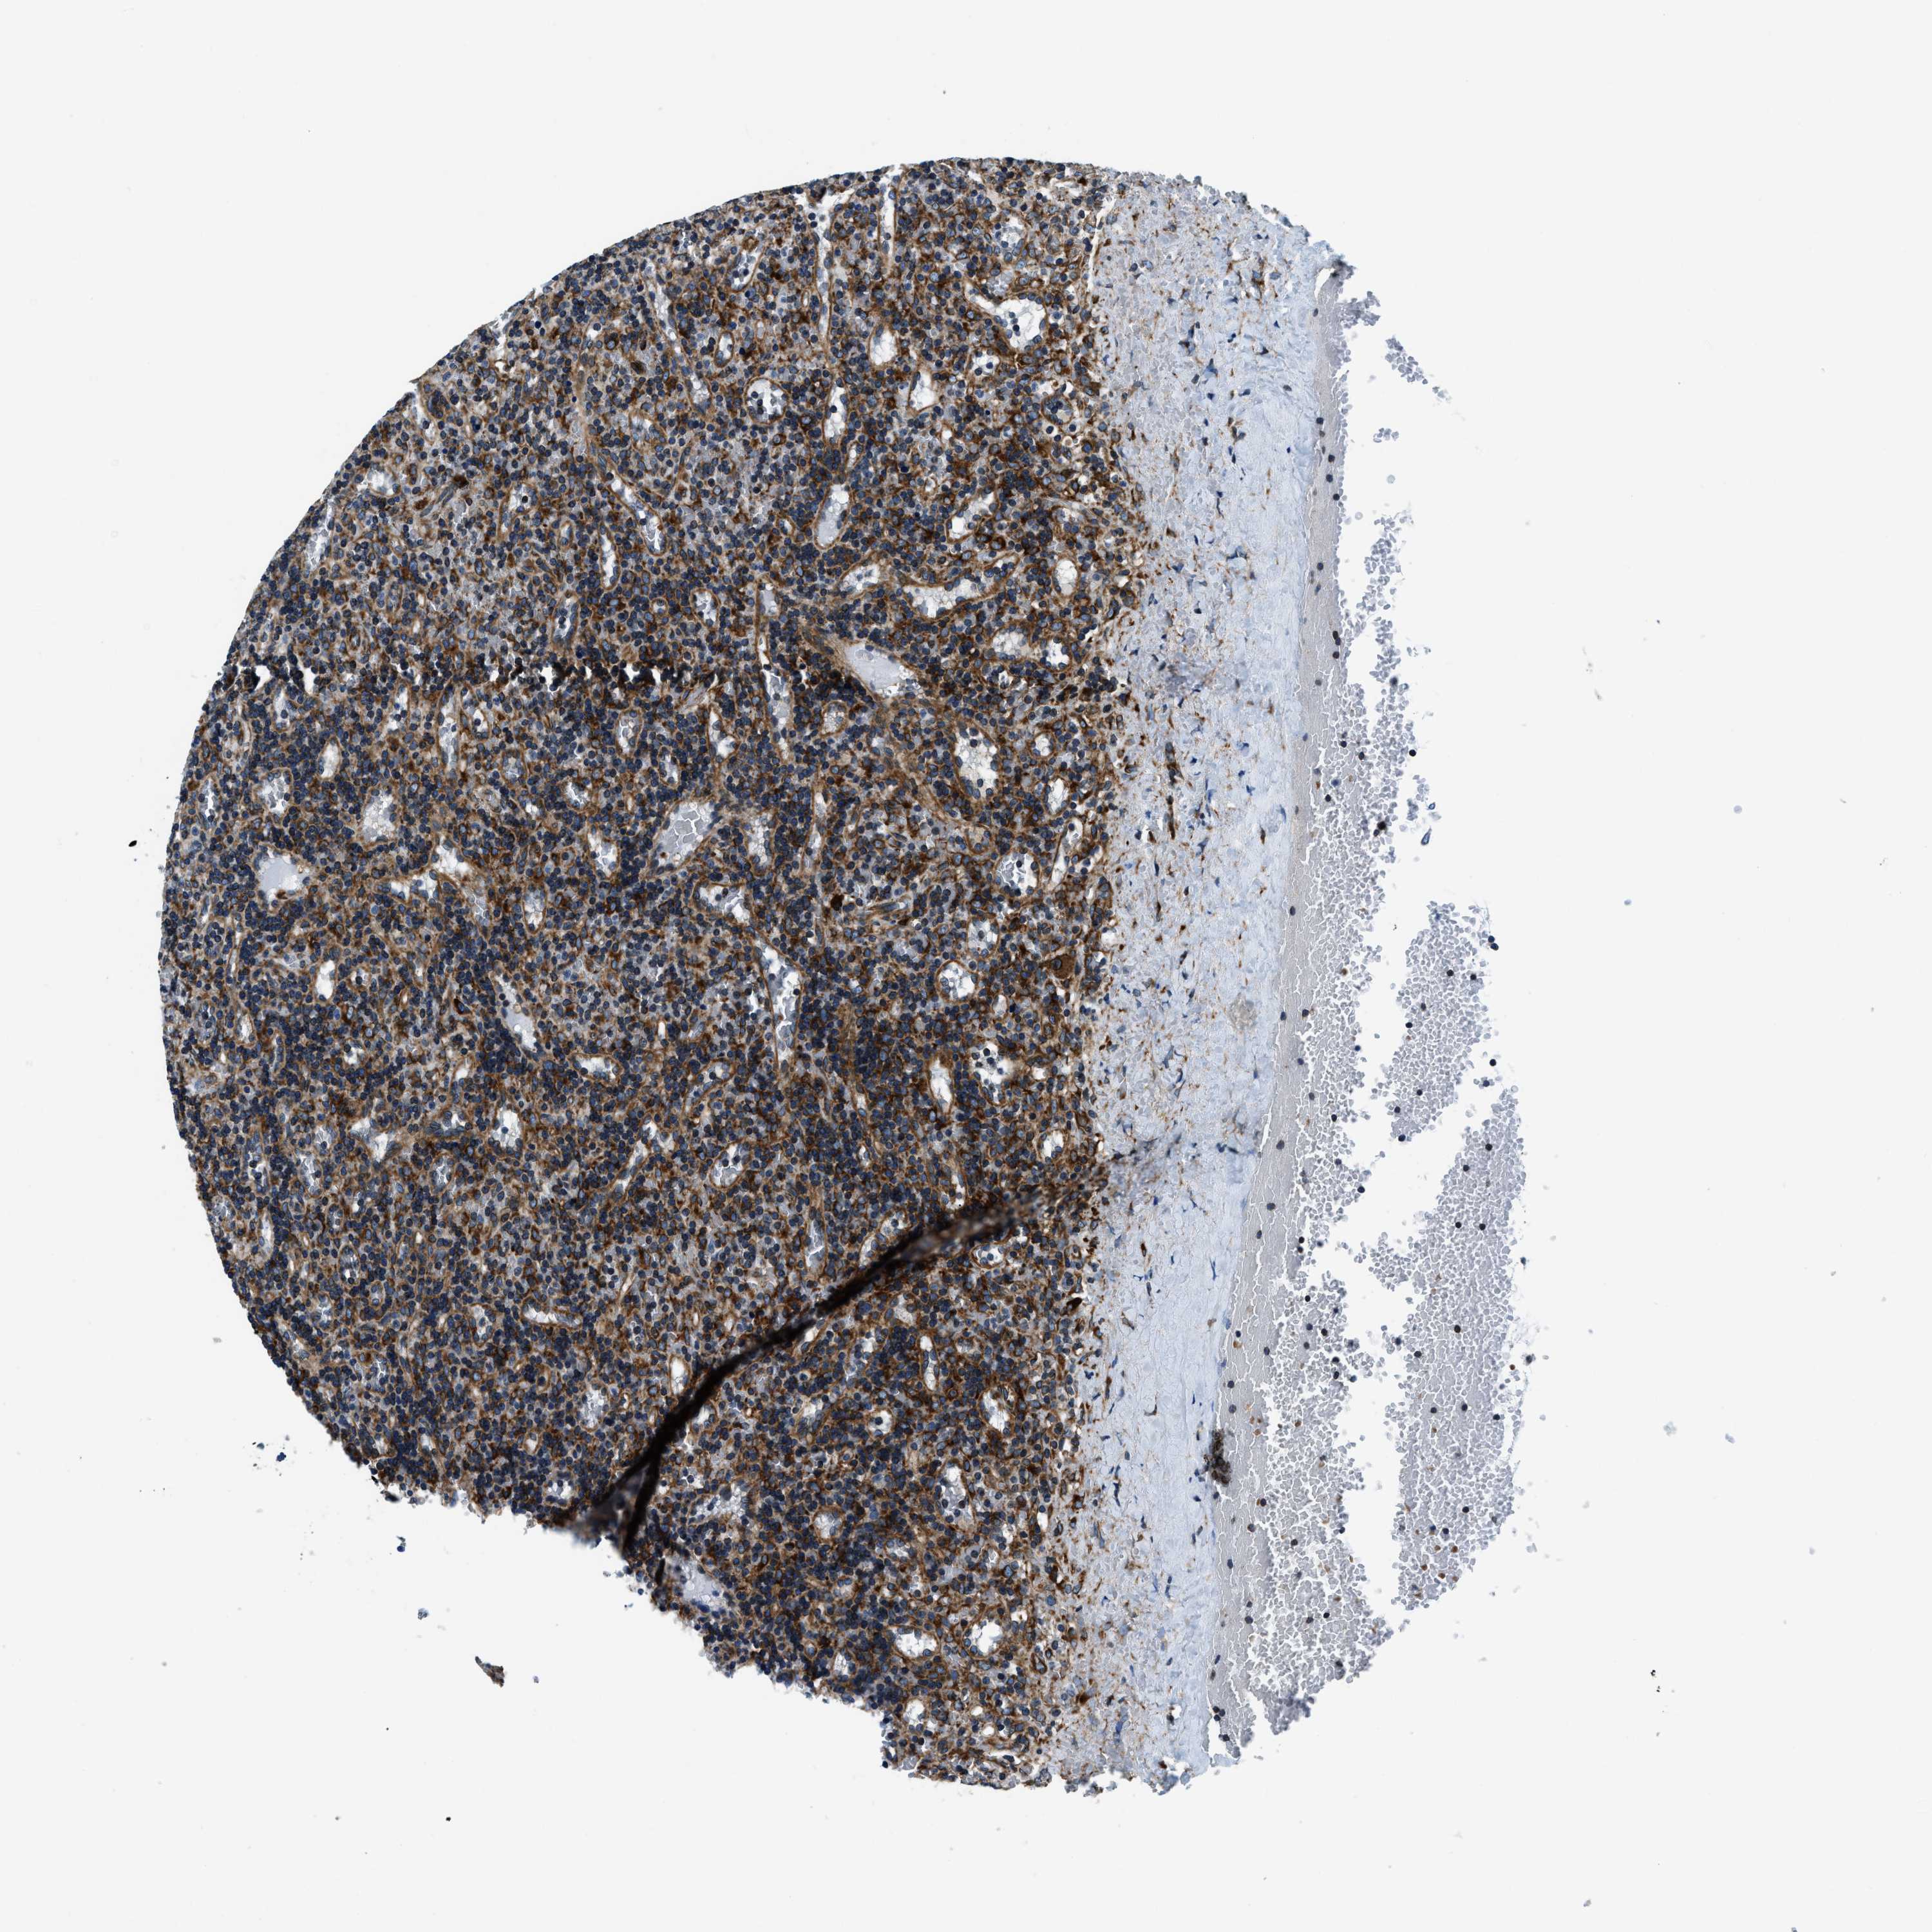

LYMPHOMA - Protein expressioni

A mouse-over function shows sample information and annotation data. Click on an image to view it in a full screen mode. Samples can be filtered based on level of antibody staining by selecting one or several of the following categories: high, medium, low and not detected. The assay and annotation is described here.

Each image is clickable and will lead to virtual microscopy that enables deeper exploration of all samples and also displays staining intensity scores, fraction scores and subcellular localization as well as patient and tissue information for each sample.

Antibody HPA019698

Staining

High

Intensity

Strong

Quantity

>75%

Location

Nuclear

Cytoplasmic/membranous

Hodgkin's disease, NOS

Malignant lymphoma, non-Hodgkin's type, High grade

Malignant lymphoma, non-Hodgkin's type, Low grade